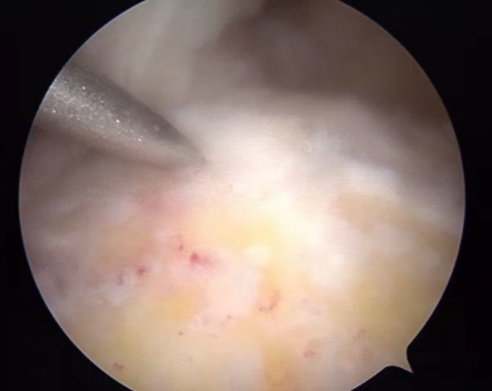

术前详细查体、评估影像学资料,发现此例患者为可修复巨大肩袖撕裂,运动医学科团队在术中充分松解关节间隙后运用 Mason-Allen 减张双排缝合技术修复肩袖,探查肩袖修复强度可靠。